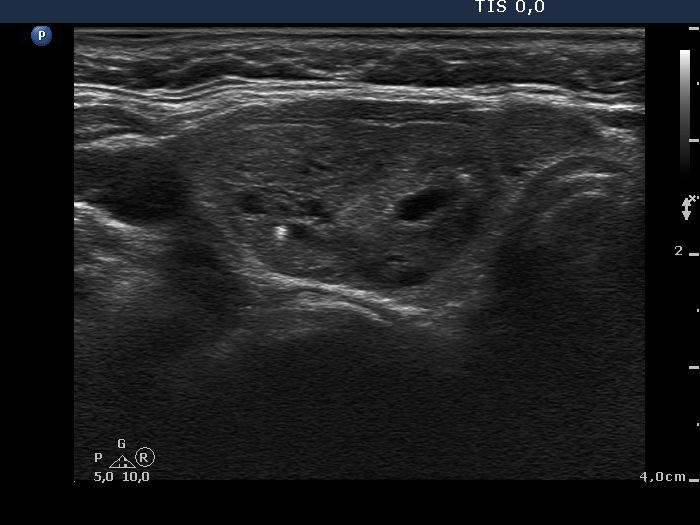

Ethanol sclerotherapy: toxic nodules - Case 2

First session of repeated therapy (ultrasonographic picture 1)

Right lobe, horizontal scan. The nodule increased significantly over time and became again moderately hypoechogenic.